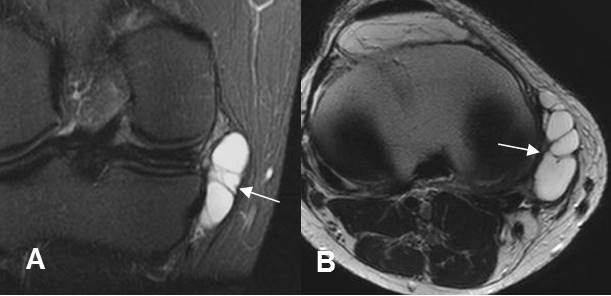

Fig 168. Bursitis anserina.

A: RM coronal en STIR y B: RM axial en T2. Lesión quística septada, en relación con los

tendones de la pata de ganso, que corresponde a bursitis.